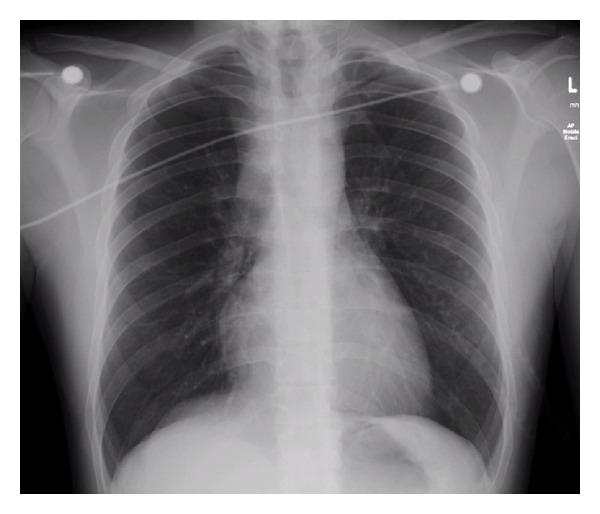

Respiratory failure due to subglottic stenosis is a rare but serious condition. A 22-year-old male presented to the emergency department (ED) with shortness of breath, stridor, and change in tone of voice. The patient did not complain of B-symptoms (fever, weight loss, and night sweats). In the week before this presentation, he was diagnosed with an upper respiratory tract infection with associated bronchospasm and discharged on oral antibiotics and inhaled salbutamol without effect. He developed hypercapnic respiratory failure in the ED after a coughing episode. A normal nasopharyngoscopic examination and a subtle mediastinal abnormality on chest radiograph lead to a working diagnosis of retrosternal subglottic obstruction. The complexities of his airway management and suggestions for multidisciplinary approach are discussed.